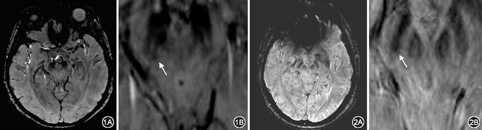

共收集47例患者。47例患者组"燕尾征"均消失。最终42例患者临床确诊为PD,2例多系统萎缩,2例特发性震颤,1例帕金森叠加综合征。PD患者中男29例,女13例,年龄范围52~80岁,平均年龄67岁。健康志愿者27名,年龄范围55~79岁,平均年龄68岁。健康对照组中有2例单侧显示不清。运用非参数秩和检验分析,"燕尾征"消失在患者组与健康对照组差异有统计学意义(Mann–Whitney U=67.500,P=0.000)。"燕尾征"消失对于诊断PD有意义。以临床诊断为标准,以"燕尾征"消失作为提示诊断PD的判断标准,敏感度为95.5%(42/44),特异度为83.3% (25/30),准确性为90.5%(67/74)(图1, 图2)。

PD病理特点是存在于黑质中的多巴胺能神经元进行性缺失[1]。先前研究发现黑质中存在5个黑质小体,且最大的黑质小体–1是主要影响PD病理改变的结构[2,3]。黄新明等[4]发现PD患者黑质铁沉积明显多于正常人,黑质在图像上表现为类圆形的低信号区。正常人黑质致密部含有大量黑色素,在图像上表现为均质低信号区,而黑质小体–1表现为逗号、条状高信号区。黑质小体–1与背侧黑质、腹侧内侧丘系共同组成形似"燕尾"样[5]。随着PD患者病理改变,大量铁在黑质小体–1沉积,使其信号降低,特有的"燕尾征"消失[6,7]。

多回波采集的重度T2*加权的三维梯度回波序列(E–SWAN)是在磁敏感加权技术的基础上发展而来,它提高了信噪比和增强信号差异,能更好的观察黑质小体–1。本次研究着重在E–SWAN幅度图上观察"燕尾征"并试图探讨"燕尾征"消失与PD的关系。

在本研究中,PD患者与健康对照组,"燕尾征"消失差异有统计学意义(P=0.000)。说明正常人"燕尾征"存在,PD患者"燕尾征"消失。以"燕尾征消失"作为提示诊断PD的判断标准,敏感度为95.5%(42/44),特异度为83.3% (25/30),准确性为90.5%(67/74)。说明"燕尾征"消失对PD有较好的诊断效能。但本研究结果敏感度低于先前研究,健康人中有2例出现单侧"燕尾征"消失,我们认为由于"燕尾征"仅出现在中脑特定层面,解剖各异性与头动均会影响"燕尾征"观察。特异度跟先前研究相同,基本符合约2%超过50岁的非PD患者(多系统萎缩、特发性震颤等)的黑质小体无法观察的流行病学[8]。本次研究也发现,部分PD患者曾使用美多巴进行治疗,我们发现"燕尾征"的消失与服用药物无关(P=0.833)。美多巴为多巴胺的合成前体,使用多美巴补充纹状体中的多巴胺,使之与乙酰胆碱系统平衡,其与黑质的铁沉积无关[9]。本研究还分析Hoehn–Yahr分期与"燕尾征"消失的关系,我们发现"燕尾征"的消失与分期差异无统计学意义(P=0.189),说明PD发病后"燕尾征"的形态就会出现变化。以上说明"燕尾征"消失对PD预后、分期意义不大。回顾以往研究发现"燕尾征"消失的诊断价值高于定量测定黑质FA值[10]、黑质区铁沉积[5]等方法,因此"燕尾征"消失对PD有较高的诊断价值。